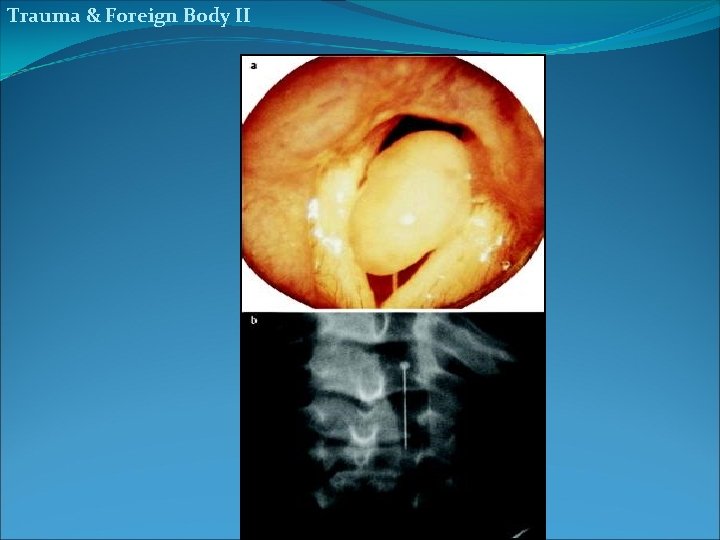

Trauma & Foreign Body II hair pin flesh bolus 21

Trauma & Foreign Body II hair pin flesh bolus 23